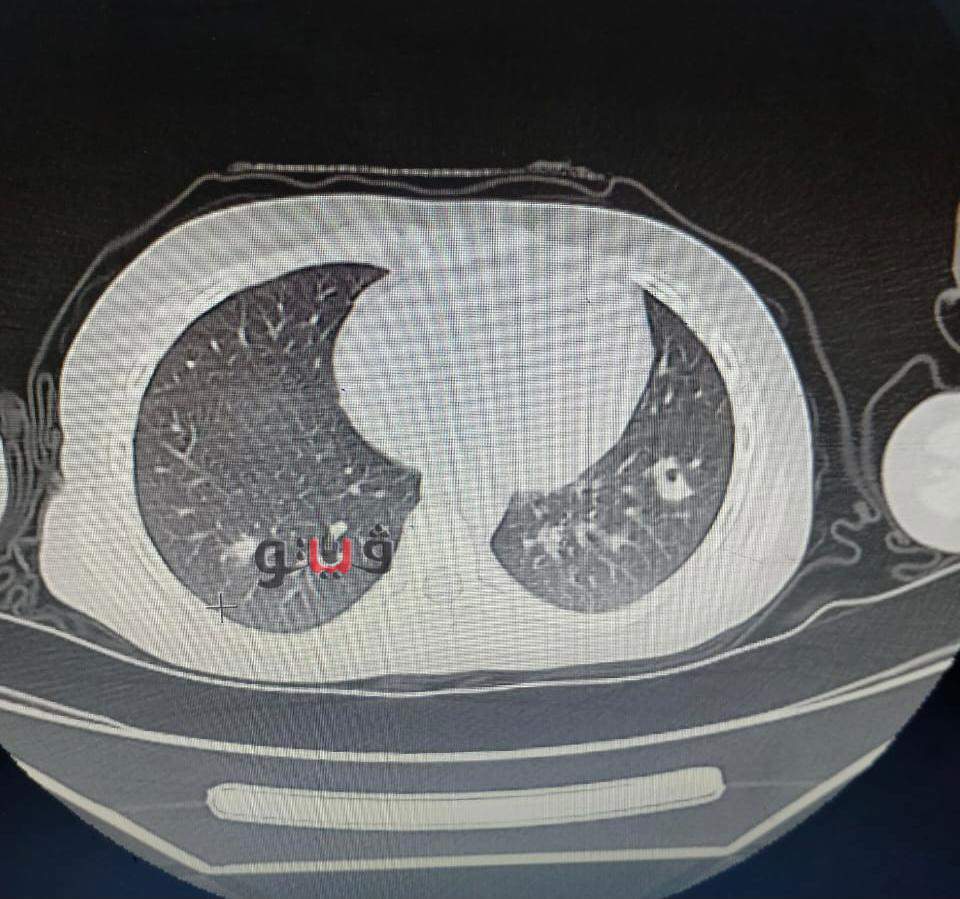

وأكد مدير مستشفى الأطفال أن الطفلة جاءت إلى المستشفى والتشخيص لحالتها كان في البداية غير مفهوم ولكن بعد الفحوصات وتشكيل فريق طبي، وعمل رنين تبين أن الطفلة لوما تعاني من ٢ خراج على المخ وخراج على الرئة وتسمم في الدم .

وقال مدير مستشفى الأطفال: الحمد الله اجتهادنا كفريق طبي مكون من الدكتورة ميادة عاطف، تخصص أمراض معدية وفريق من الجراحين قام بتفريغ الصديد من المخ وخرجت لوما من المستشفى، والحمد لله كتب الله لها الشفاء.